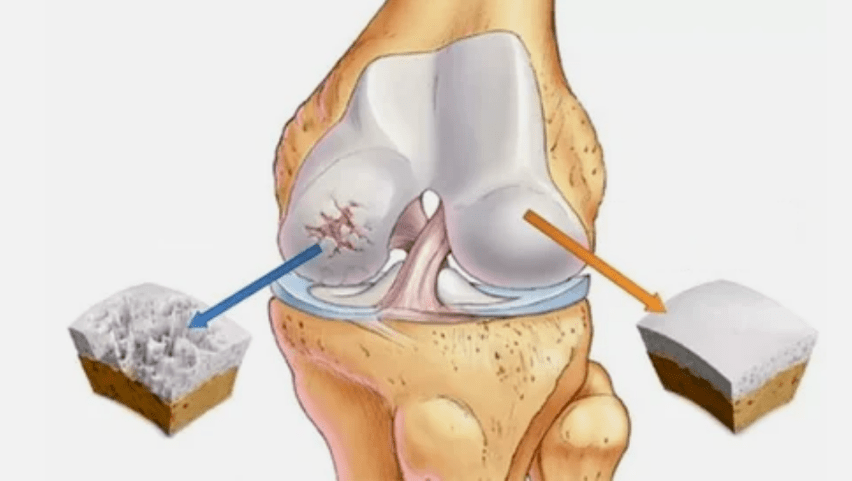

- Hyalin estaldura patologiak. Kartilagoaren mehatzeak bere ehun patologikoak ordezkatzea eragiten du - hezur egiturak.

- Hazkunde anomaloak kartilagoan agertzen dira - osteofitoak.

- Artikuluaren hutsunea murriztea, irudian nabarmentzen dena. Urraketaren etapa diagnostiko-tantgenologoak zehazten du. Gaixoak konplexutasuna edo ezintasuna sentitzen du gorputz-adarra erabat zuzentzeko eta okertzeko;

- Batera-deformazioa, kartilagoak forma irregularra eskuratzen du, kurbadura probokatzailea;